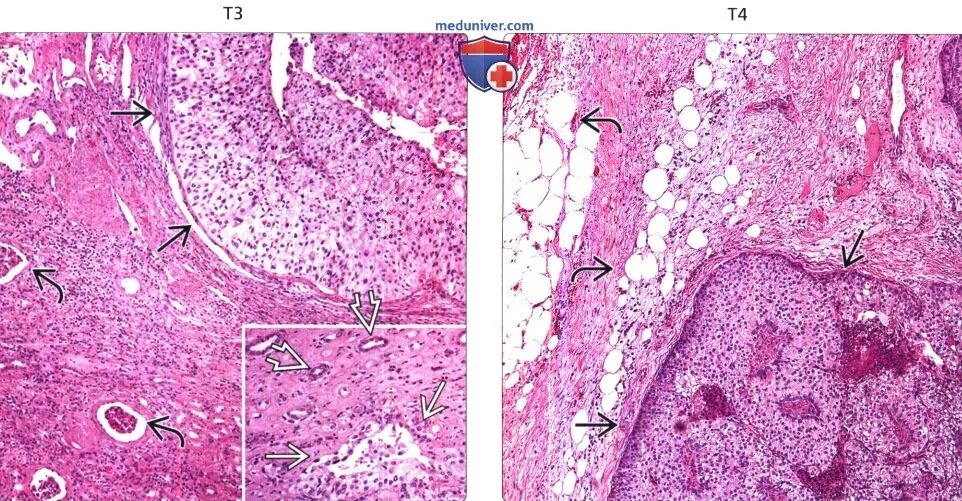

Может ли гистология ошибаться